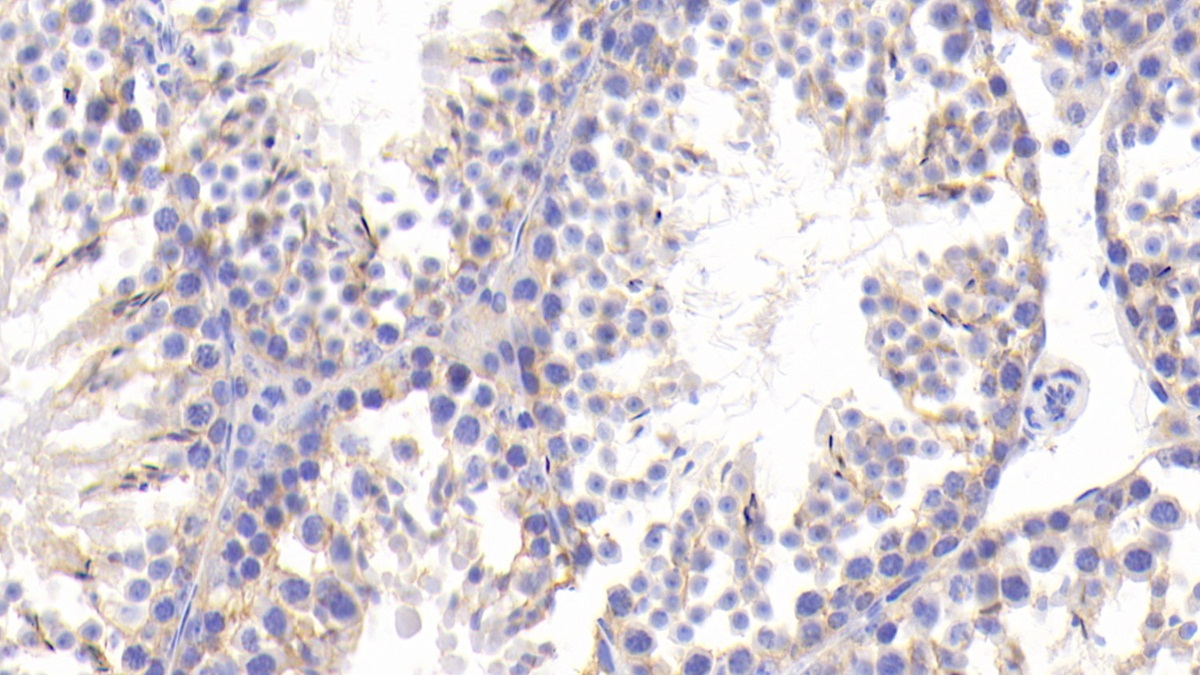

Polyclonal Antibody to Microtubule Associated Protein 1B (MAP1B) (PAC975Mu01)

| Валидировано для | IHC Иммуногистохимия |

| Рекомендуемые разведения | WB: 0.5-2 мкг/мл; 1:500-2000; IHC: 5-20 мкг/мл; 1:50-200; ICC: 5-20 мкг/мл; 1:50-200; Оптимальное разведение определяется конечным потребителем |